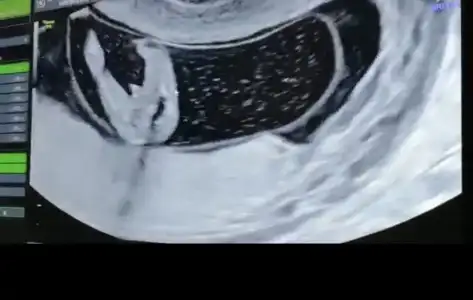

- Janna - - Janna - canım sen bana kız dedin çoğu kişi kız dedi 😅 doktor da ilk salı günü kıza benziyor gibi demişti ama bana bugün pipi resmi verdi, Allah aşkına sende bak 🤣 kafam karıştı cidden

Bu saatten sonra pek dönmez gibi dedi sonra da baktı bi iyice erkek bu erkek dedi.

Muayene zamanın geçmeden bi daha gelirsin bi daha bakarız dedi

Ekliyorum buraya fotoyu daha doğrusu anlayan herkes benim kafam karıştı..

yok artık benim bile kafam karıştı şaşırdım erkekmi şimdi kesin hani yuvarlak kese kızdı btün teoriler yalan oldu bende benimki herhalde erkek diyodum dahada meraklandım şimdi😂

Kızlar Dilos6342 Dilos6342 cinsiyet tahmini ile ilgili değişikliği yazınca bende bi tereddütte kaldım. Bize de 12+5. de resimlerdeki yerlere zoom yaparak erkek demişti. - Janna - - Janna - ne diyorsun bu erkek görüntüsü mü 😅